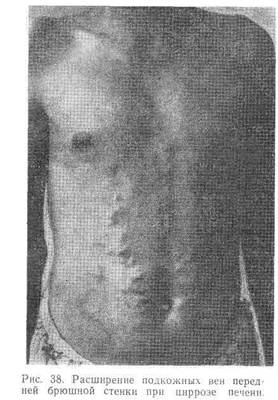

При выраженной портальной гипертензии на коже живота, вначале на боковых поверхностях, обнаруживается расширение подкожных вен («голова медузы»). Нередко наблюдаются расширение прямокишечных вен, иногда тяжелые кровотечения из них, а также варикозное расширение нижних вен пищевода, реже — в области кардиального отдела желудка, при разрыве которых могут возникнуть угрожающие для жизни больного кровотечения, в большинстве случаев в виде кровавой рвоты.

При физическом обследовании брюшной полости в ряде случаев отмечается метеоризм, часто расширение подкожных вен живота (рис. 38). Как правило, в начальной стадии печень увеличенная, плотная, с заостренным краем; часто прощупывается увеличенная селезенка.